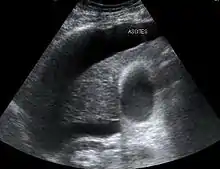

HRS can affect individuals with cirrhosis, severe alcoholic hepatitis, or liver failure, and usually occurs when liver function deteriorates rapidly because of a sudden insult such as an infection, bleeding in the gastrointestinal tract, or overuse of diuretic medications. HRS is a relatively common complication of cirrhosis, occurring in 18% of people within one year of their diagnosis, and in 39% within five years of their diagnosis. Deteriorating liver function is believed to cause changes in the circulation that supplies the intestines, altering blood flow and blood vessel tone in the kidneys. The kidney failure of HRS is a consequence of these changes in blood flow, rather than direct damage to the kidney. The diagnosis of hepatorenal syndrome is based on laboratory tests of individuals susceptible to the condition. Two forms of hepatorenal syndrome have been defined: Type 1 HRS entails a rapidly progressive decline in kidney function, while type 2 HRS is associated with ascites (fluid accumulation in the abdomen) that does not improve with standard diuretic medications.

In contrast, type 2 HRS is slower in onset and progression, and is not associated with an inciting event. It is defined by an increase in serum creatinine level to >133 μmol/L (1.5 mg/dL) or a creatinine clearance of less than 40 mL/min, and a urine sodium < 10 μmol/L.[7] It also carries a poor outlook, with a median survival of approximately six months unless the affected individual undergoes liver transplantation. Type 2 HRS is thought to be part of a spectrum of illness associated with increased pressures in the portal vein circulation, which begins with the development of fluid in the abdomen (ascites). The spectrum continues with diuretic-resistant ascites, where the kidneys are unable to excrete sufficient sodium to clear the fluid even with the use of diuretic medications. Most individuals with type 2 HRS have diuretic-resistant ascites before they develop deterioration in kidney function.[8]